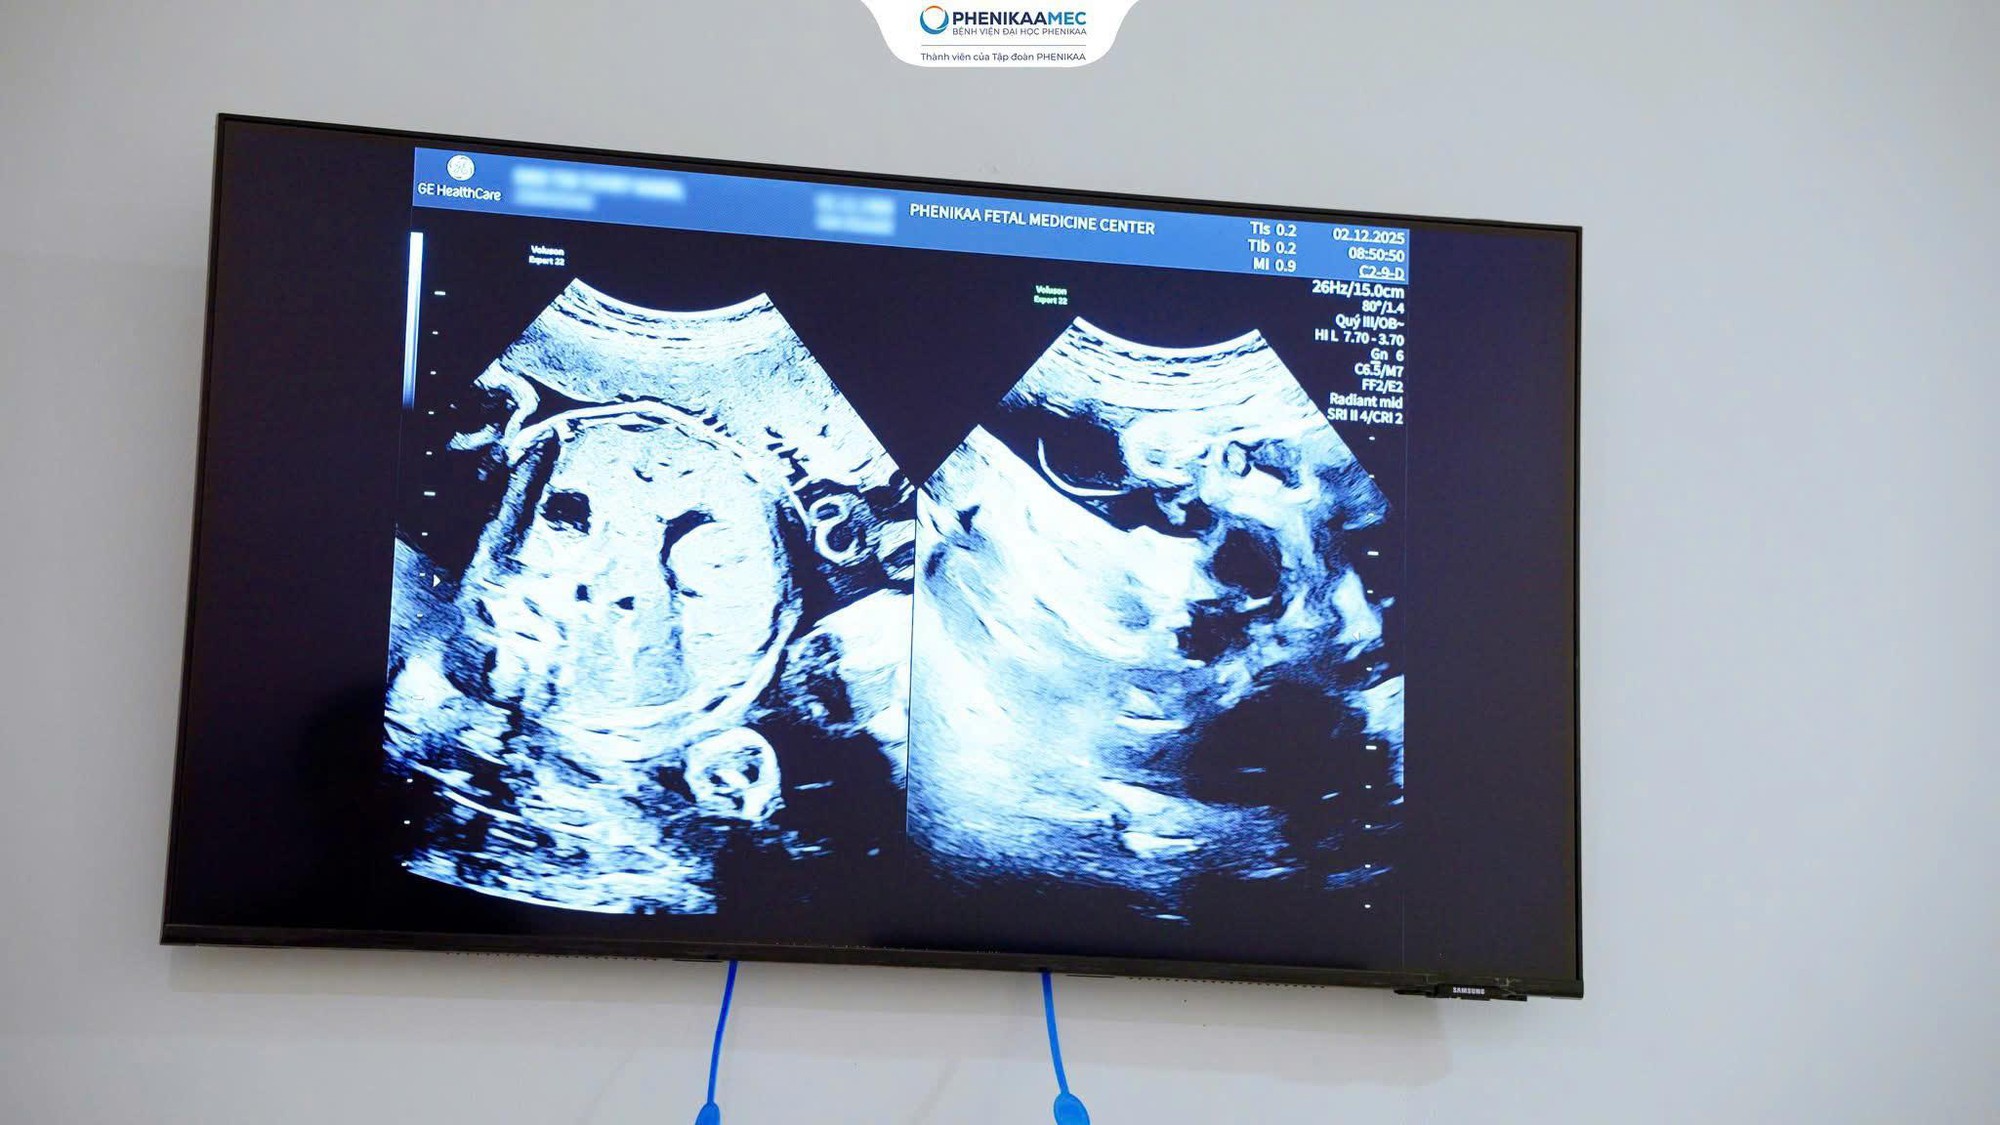

Hình ảnh siêu âm song thai, rau tiền đạo trung tâm được phát hiện và quản lý cá thể hóa tại Trung tâm Y học Bào thai PhenikaaMec